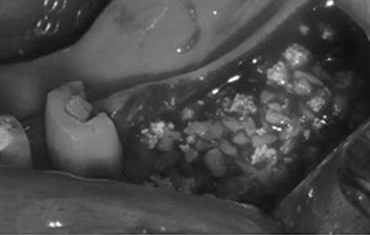

타 치과의 뼈 이식 후 골조직

램브란트치과 상인점 뼈이식 후 골조직

치료 후윗턱뼈 공기주머니에 뼈이식

치료 전

치료 후